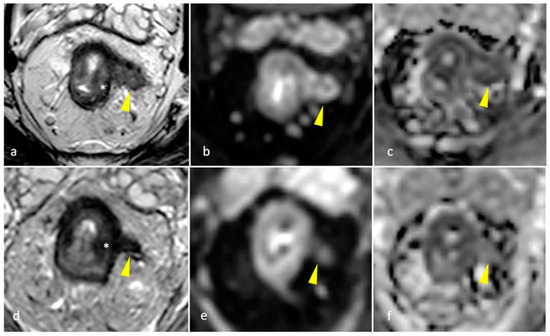

- Kalisz, K.R.; Enzerra, M.D.; Paspulati, R.M. MRI Evaluation of the Response of Rectal Cancer to Neoadjuvant Chemoradiation Therapy. Radiographics 2019, 39, 538–556. [Google Scholar]

- Jang, J.K.; Choi, S.H.; Park, S.H.; Kim, K.W.; Kim, H.J.; Lee, J.S.; Kim, A.Y. MR tumor regression grade for pathological complete response in rectal cancer post neoadjuvant chemoradiotherapy: A systematic review and meta-analysis for accuracy. Eur. Radiol. 2020, 30, 2312–2323. [Google Scholar] [CrossRef]

| mrTRG | 1 | Complete Radiologic Response (i.e., no evidence of tumor) |

| 2 | Good Response (i.e., dense >75% fibrosis with no obvious residual tumor) | |

| 3 | Moderate Response (i.e., >50% fibrosis or mucin with a minority of visible tumor) | |

| 4 | Slight Regression (i.e., <50% fibrosis or mucin with a majority of visible tumor) | |

| 5 | No post-treatment changes | |